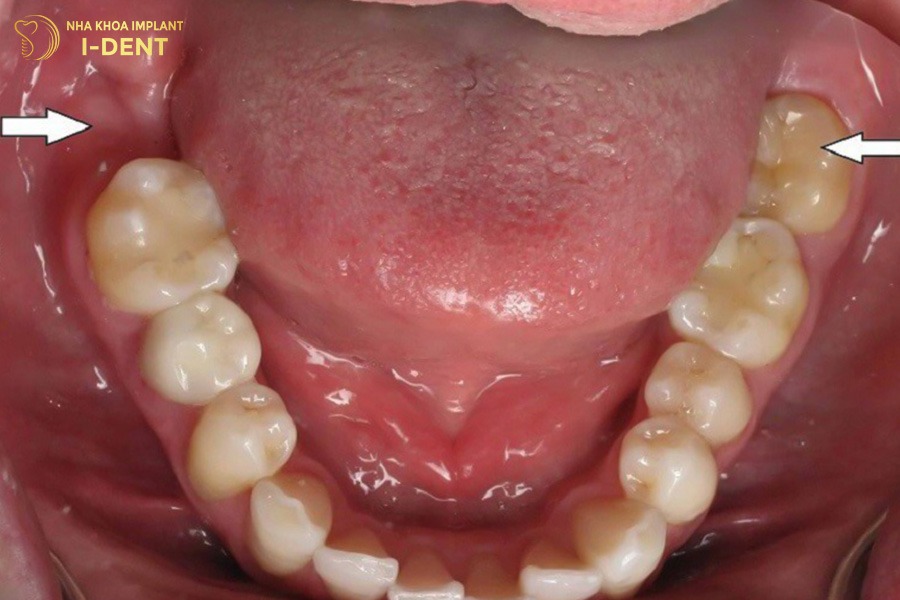

Răng số 7 nằm giữa răng số 6 và răng khôn trên cung hàm, thường mọc vĩnh viễn vào khoảng năm 12 tuổi và chỉ mọc duy nhất một lần trong đời. Điều này đồng nghĩa nếu bị mất răng số 7, chiếc răng này sẽ không thể tự mọc lại. Vì vậy, khi bị mất răng số 7 cần điều trị sớm để tránh ảnh hưởng đến chức năng ăn nhai và cấu trúc hàm về lâu dài.

Vị trí của răng số 7